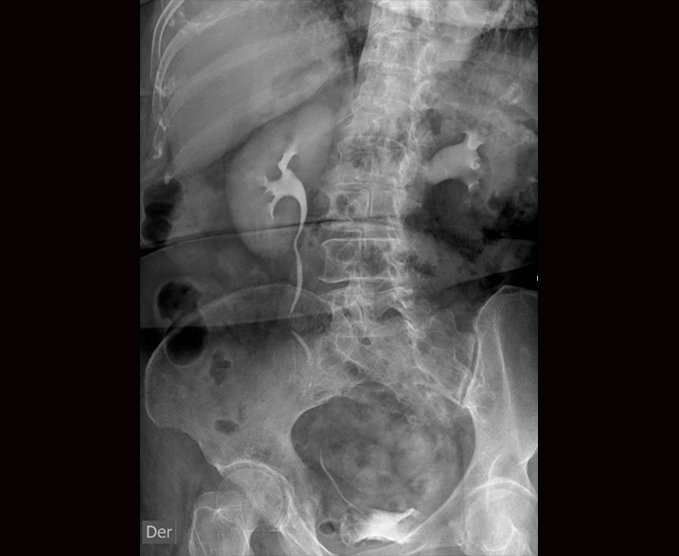

Algunos de nuestros estudios contrastados.

- Urografía excretora